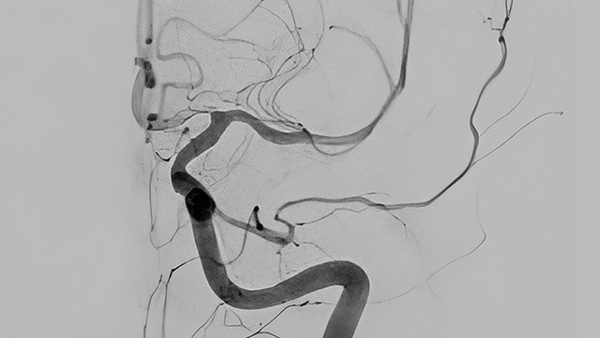

What happens when you take one of the best flow diverters in use today and engineer surface modification?

Enter the new generation of flow diverters and find out, join René CHAPOT (Germany) and Markus MÖHLENBRUCH (Germany) as they introduce the FRED X.

Discover the nature of the surface modification. Learn how FRED X was designed to reduce the rate of thrombose production on the device itself and how, in early clinical experience, it demonstrated similar rates of occlusion to FRED, but with the promise of less thrombogenicity which is associated with older iterations of flow diverters.

Our two experts go on to speak about how the FRED X surface modification allowed for using only mono-aggregation in these initial clinical cases, with Markus MÖHLENBRUCH pointing to the good outcomes obtained with FRED X at 3 to 6 months follow-up, as well as showing an excellent safety profile.

With FRED X, Microvention is poised to enter the next chapter in aneurysm treatment. The early clinical experience discussed here demonstrates a novel device that can be used with mono-aggregation, has had few complications, and holds the potential of being able to be employed in the treatment of both unruptured and ruptured aneurysms.